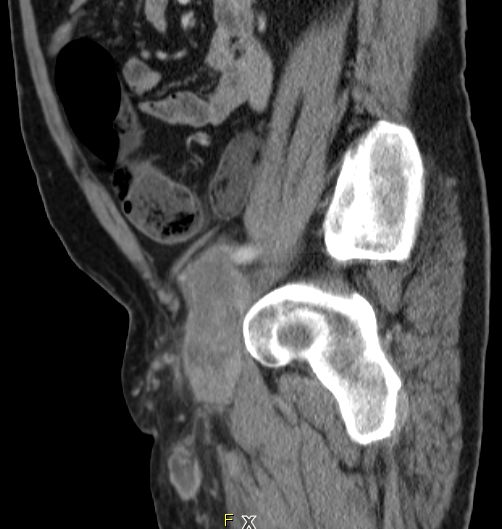

| Leiste | 72-jähriger Landwirt mit einem Leiomyosarkom der linken Leiste pT2b pN0 G2 R0. 110 x 50 x 50 mm großer, solider Tumor mit enger Lagebeziehung zum Gefäßbündel.

Infiltration des Musculus rektus abdominis.![]() |

![]() |

![]() | ||